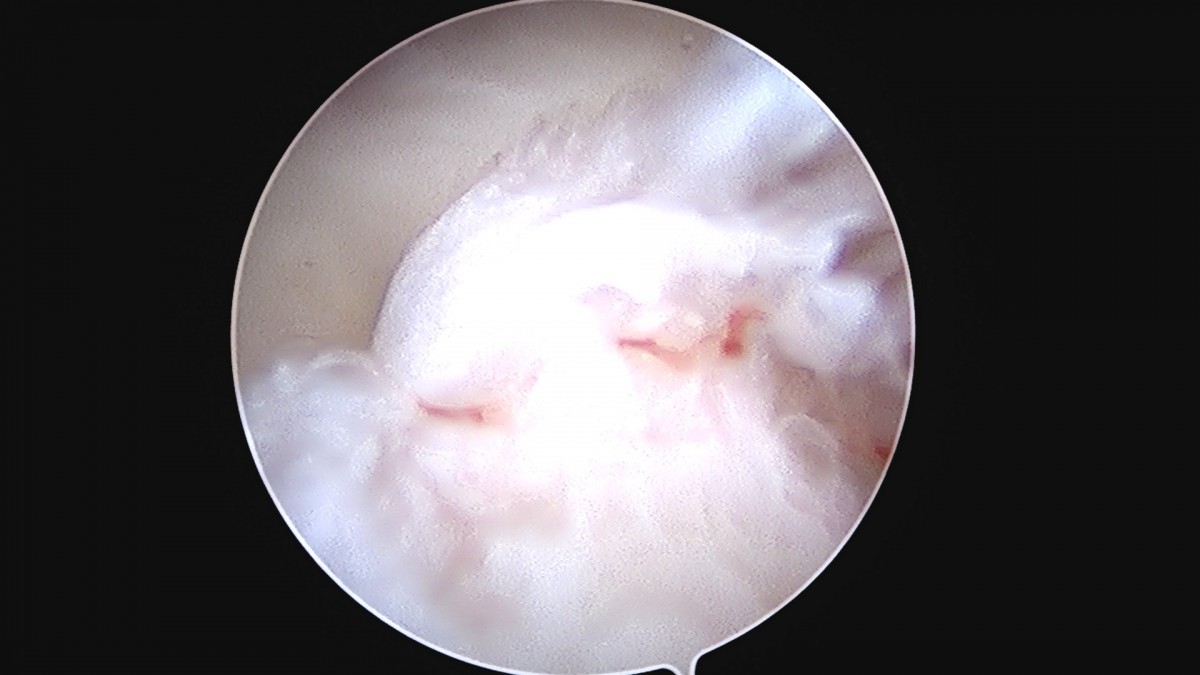

정지영원장님 손목 삼각섬유연골 복합체 봉합술 박현O 환자

dae765e4d9ac96aee867c9d6292d8784_1758009004_9063.jpg